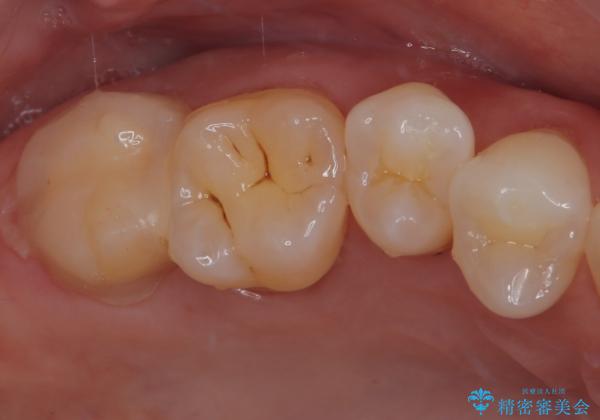

まずは根管治療を行い、症状が消退したことを確認してオールセラミッククラウンにて補綴治療を行うこととしました。

根管治療を行った奥歯は、再発防止や残された歯質を守るため、クラウンによる補綴治療が必要となります。

補綴後6ヶ月経過しレントゲンを撮影したところ、根尖周辺の病変が消失していることが確認できました。